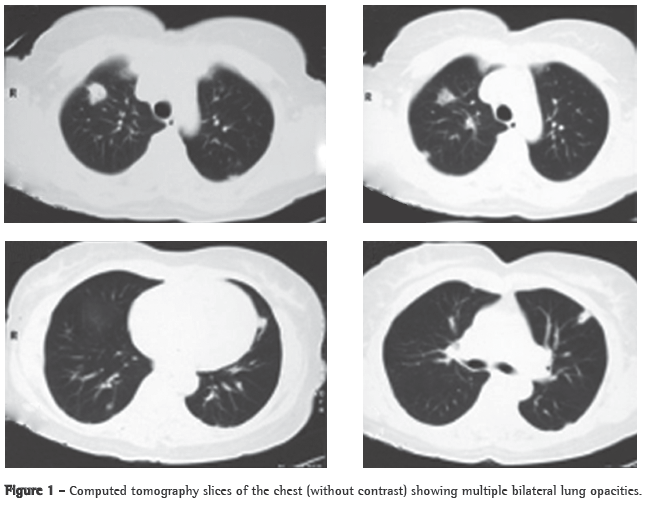

A 56-year-old Caucasian female sought treatment in the emergency room presenting a painful, right-sided neck tumor for 5 days. The patient reported a dry cough and high fever for 3 days. She described herself as a nonsmoker. She was hypertensive and diabetic. She had experienced a myocardial infarction 3 years prior. At admission, the patient was dehydrated and afebrile (axillary temperature, 36.7°C). She presented normal respiration. Laboratory tests revealed increased erythrocyte sedimentation rate (92 mm). Ultrasound of the neck showed IJV thrombosis, and anticoagulation was started on post-admission day 4. A chest X-ray demonstrated at least two nodules in the left lung, one apparently cavitated and one with a diameter of 18 mm at its base, as well as an irregular lesion, 25 mm in diameter, in the right upper lung lobe. A transesophageal echocardiogram, performed in order to rule out endocarditis, demonstrated no vegetation. Due to the hypothesis of pneumonia, empirical treatment with oral cefuroxime (500 mg every 12 h) was started. A computed tomography scan of the chest revealed multiple bilateral lung opacities, with an aspect suggestive of metastatic implants (Figure 1). The patient was then submitted to fiberoptic bronchoscopy, the findings of which were normal. In the microbiological analysis of the bronchoalveolar lavage fluid, testing for acid-fast bacilli and fungi were negative, as were the cytopathologic study and cultures. Since the working diagnosis was metastatic neoplasm, the patient underwent surgical lung biopsy. The anatomopathological examination of the sample showed chronic suppurative inflammation with organizing abscesses in lung parenchyma. In view of the hypothesis of Lemierre's syndrome caused by jugular thrombosis accompanied by septic pulmonary embolism, the patient was questioned regarding the occurrence of tonsillitis at the onset of the disease. The patient had no recollection, but her daughter remembered that the patient had used oral amoxicillin (500 mg every 8 h for 10 days) for the treatment of tonsillitis some days prior to hospitalization. At hospital admission, the patient received a course of intravenous cefuroxime (750 mg every 8 h for 7 days) concomitantly with oral azithromycin (500 mg once a day for 5 days). Subsequently, because fever persisted, she was treated with cefepime (1,000 mg every 12 h for 7 days). A control computed tomography scan of the chest performed after this course of antibiotics showed nearly complete resolution of the opacities (Figure 2). The patient had been afebrile since the third day of the new course of antibiotics. No microorganisms were isolated from blood cultures or bronchoalveolar lavage cultures. Since there is no evidence that it is beneficial in cases of Lemierre's syndrome, anticoagulation was discontinued after 20 days.

The response to antibiotics is slow. The mean time between the initiation of treatment and the resolution of fever ranges from 8 to 12 days.